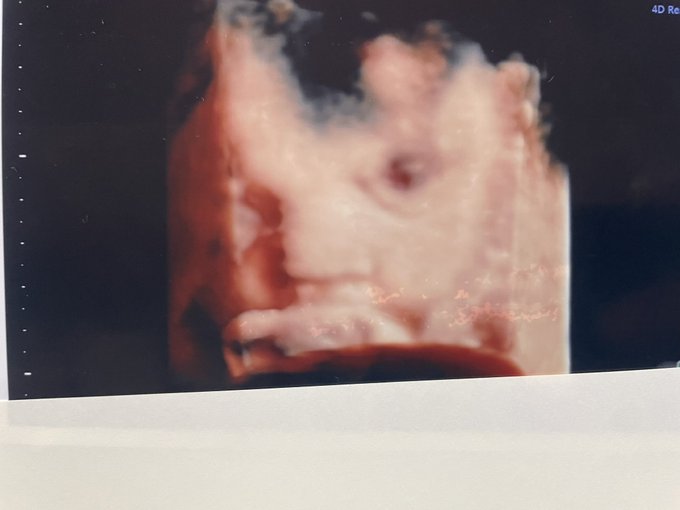

赤ちゃんの性別が判明しました👶